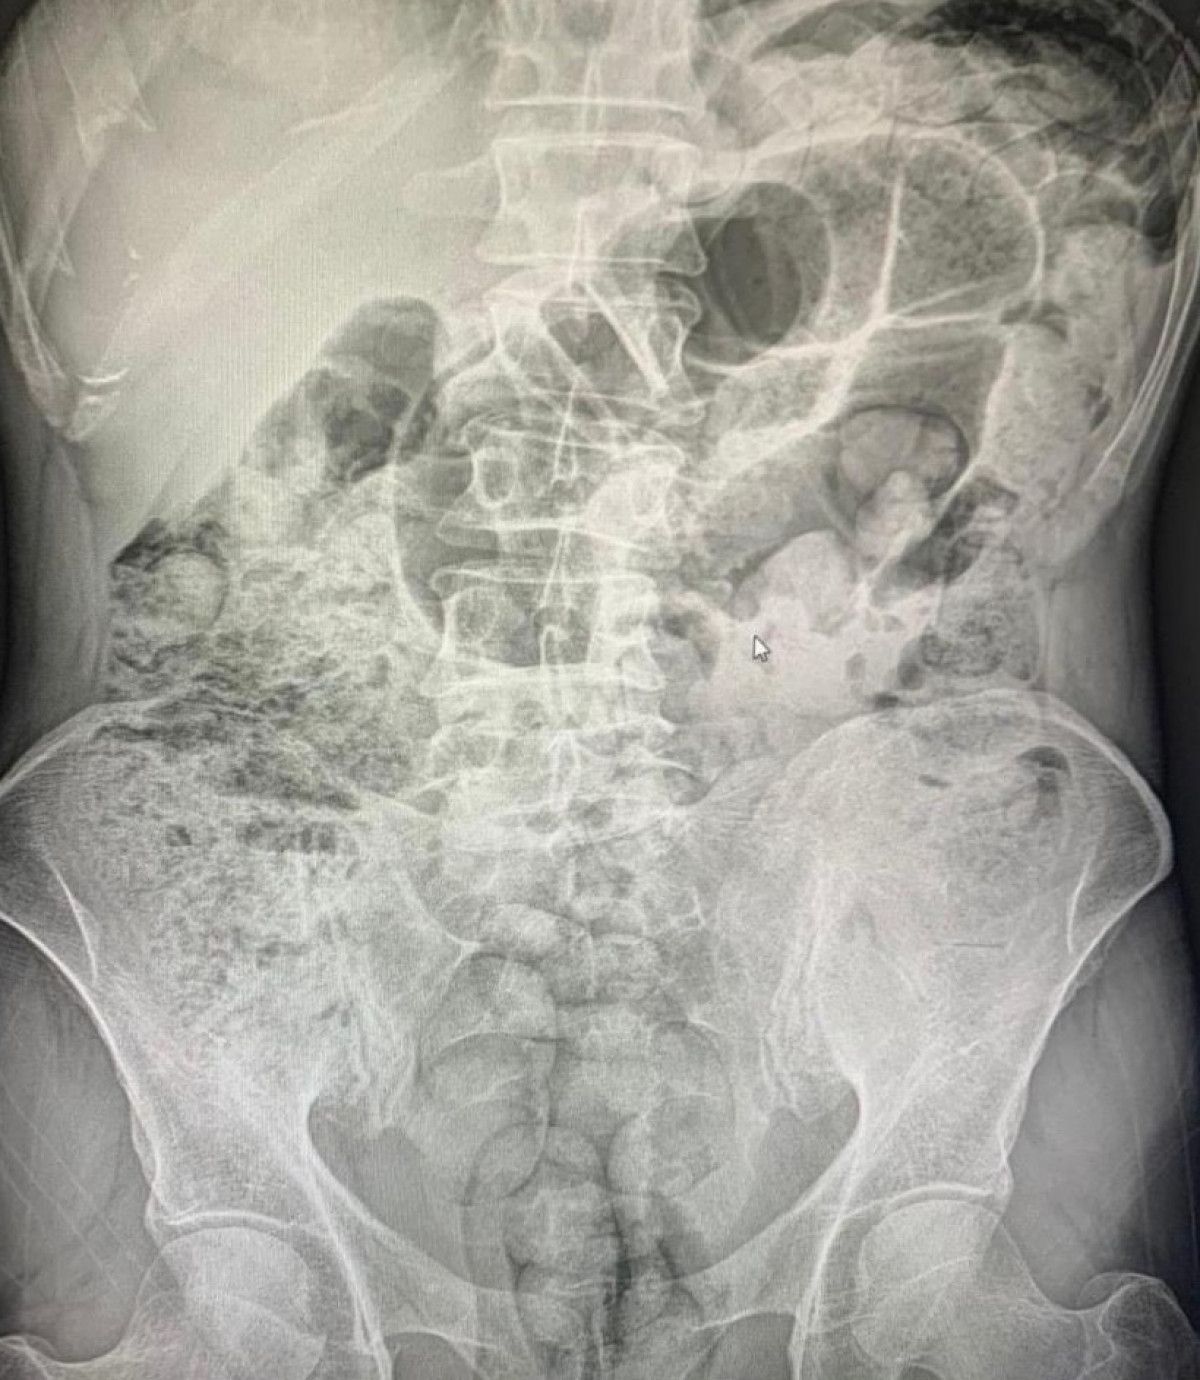

Yapılan radyolojik görüntülemeler neticesinde şüphelilerin midelerinde çok sayıda cisim olduğu belirlendi.

Zanlıların midelerinden 119 paket halinde 1 kilo 597 gram eroin ve metamfetamin çıkarıldı.